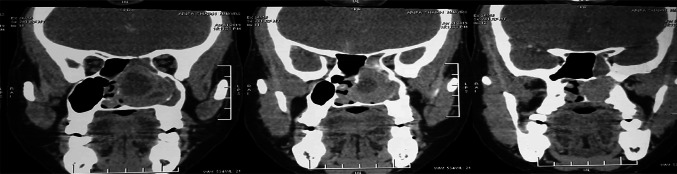

A 40-year-old female was admitted in our Department of ENT and Head-Neck Surgery in April 2019 for left chronic nasal obstruction and left nasal cavity bleeding. Endoscopic examination of nasal cavity showed a reddish vascular mass in left nasal cavity which bleed on touch. CT PNS with contrast showed ill defined enhancing soft tissue density lesion measuring 6.5 cm × 4.6 cm × 3.1 cm [AP X CC X T] involving left nasal cavity causing near total airway narrowing. It was involving left side turbinates, left ethmoid and maxillary sinuses. Marked erosion of nasal septum, bilateral cribriform plates, medial wall of left orbit, bony walls of bilateral ethmoid and left sphenoid sinuses were seen. Contralateral extension was seen involving right nasal cavity and ethmoid sinuses. Subtle intracranial extension was seen into floor of anterior cranial fossa in midline. No intra orbital extension was seen (Figs. 1, 2).

Fig. 1.

Coronal CT showing left nasal cavity mass involving left turbinates, left ethmoid and maxillary sinuses with marked erosion of nasal septum, bilateral cribriform plates, medial wall of left orbit, bony walls of bilateral ethmoid and left sphenoid sinuses. contralateral extension was seen involving right nasal cavity and ethmoid sinus

Fig. 2.

Coronal CT scan with contrast